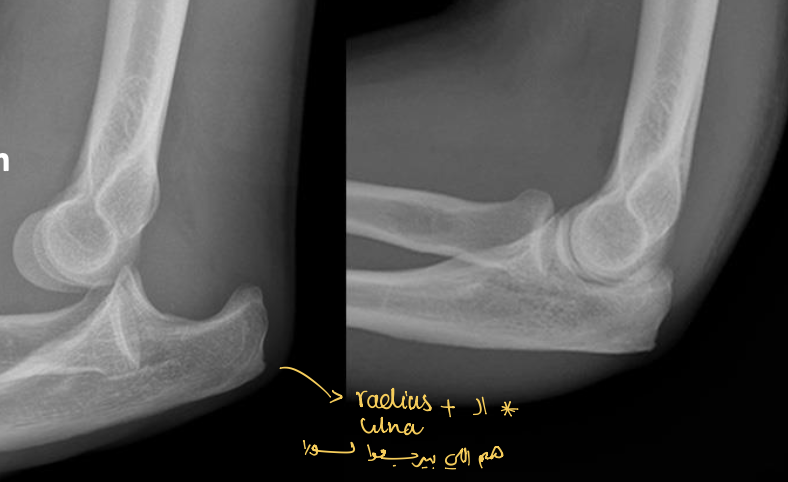

Identify the structures ? view?

AP

Elbow Joint

Elbow Joint, Lateral View